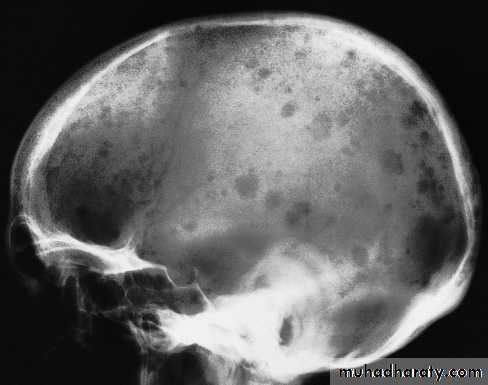

Skull X-rayBony configuration and shape

Bone densityAny Lytic lesion

Any fracture

Any calcification

Diploë, pituitary fossa, paranasal sinuses, orbits

The sutures